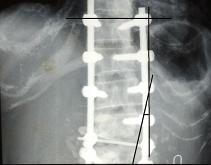

• 我院脊柱外科水平又上新台阶

我院脊柱外科水平又上新台阶

我院脊柱外科水平又上新台阶 骨脊柱一区成功开展严重侧弯合并后突畸形患者矫形手术 骨脊柱一区 陈远明 日前,我院骨脊柱一区陈锋主任...